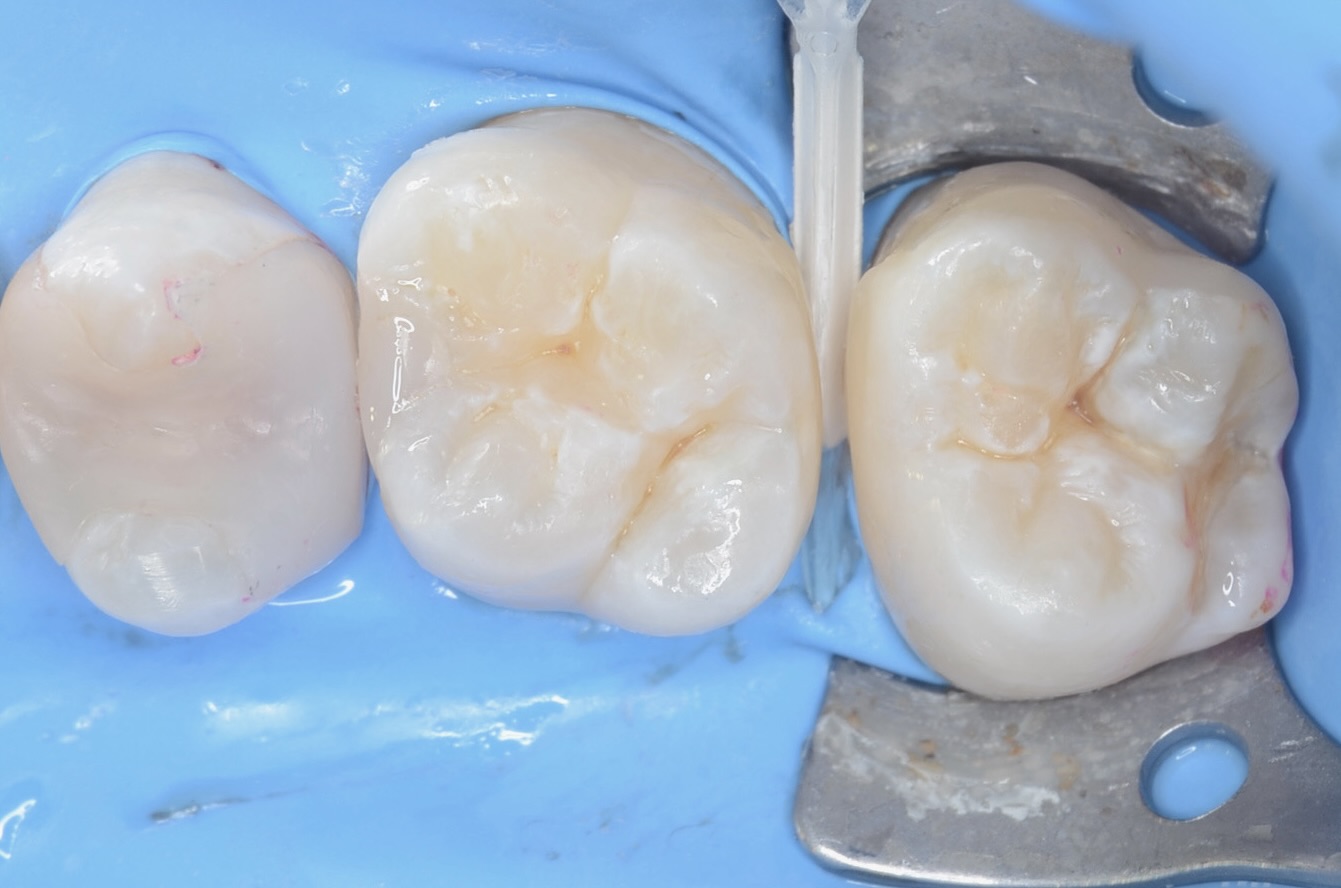

歯間離開用モジュールセット

歯間離開用の小さなゴムの輪をはの間に入れて1週間待ちます。 -

1週間後

ゴムの輪を外すと歯とはの間が少し開いています。 -

口蓋側面観

手間はかかりますがこれによって、隙間から治療することで、歯を削る量を減らします。 -

7番近心

初期虫歯に見えますが削ると中で虫歯が広がっています。 -

6番遠心の虫歯

-

完全虫歯を除去しました -

7番近心にダイレクトボンディング

広がった歯間が自然に閉じています。